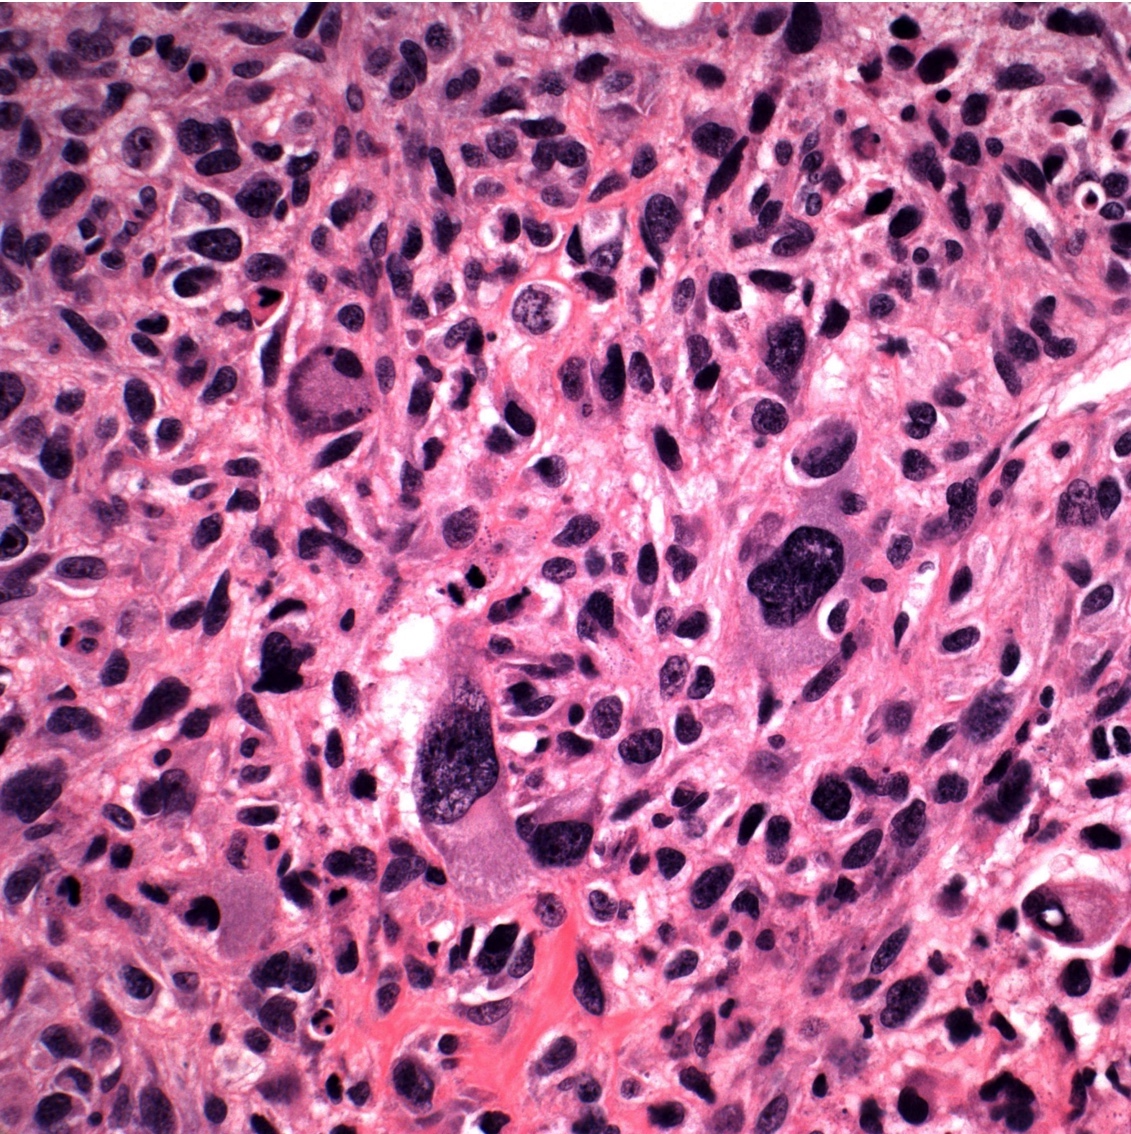

Microscopic (histologic) images

Contributed by Jesse Hart, D.O., Borislav A. Alexiev, M.D. and AFIP

- Conventional (high grade intramedullary) osteosarcoma (Eur J Cancer 2002;38:1218, Am J Clin Pathol 2006;125:555):

- Permeative growth: intramedullary permeative growth (replacement of medullary space, surrounds and erodes native trabeculae, fills Haversian systems) and cortical destruction with soft tissue invasion

- Neoplastic cells: marked atypia (pleomorphic, hyperchromatic)

- Multiple cell morphologies often present in 1 tumor (epithelioid, plasmacytoid, spindled, small round cells, clear cells, giant tumor cells)

- Mitotic figures are easily demonstrable and atypical mitotic figures may also be identified

- Neoplastic bone (necessary for diagnosis): no minimum quantity necessary

- Most common: filigree / lace-like disorganized woven bone (intimately associated with neoplastic cells)

- Broad sheets of bone

- Normalization: decreased cytologic atypia of neoplastic cells entrapped in the bone matrix

- Scaffolding (appositional neoplastic osteoid deposition): deposition of neoplastic osteoid on native trabeculae

- Nonneoplastic giant cells: ~25% of cases

- Histologic subtypes of conventional osteosarcoma: no prognostic significance

- Osteoblastic, chondroblastic and fibroblastic are based on the prominent matrix they secrete (often admixed in 1 tumor)

- Osteoblastic osteosarcoma: the predominant matrix is neoplastic bone (as described above)

- Chondroblastic osteosarcoma: the predominant matrix is high grade cartilage (never has low grade cartilage)

- Fibroblastic osteosarcoma: spindled to epithelioid cells, often with severe atypia, which may secrete extracellular collagen (may be extensive)

- Telangiectatic osteosarcoma: the tumor is multiloculated with large blood filled spaces; high grade malignant cells and neoplastic bone in septa (the imaging differential diagnosis is with aneurysmal bone cyst)

- Other morphologic variants: giant cell rich variant (numerous osteoclast-like giant cells), epithelioid variant, osteoblastoma-like variant, chondroblastoma-like variant, chondromyxoid fibroma-like osteosarcoma, clear cell variant, small cell variant

Practice question #2

A 16 year old boy had a biopsy from a 16 cm mass in the proximal humerus (see image). Which of the following is true?

Practice answer #2

C. Treatment will include neoadjuvant chemotherapy followed by resection. This is a conventional high grade osteosarcoma.